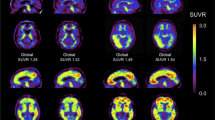

The NIA-AA research criteria using combined fluid and imaging biomarkers to diagnose AD have been proposed in 2018 [10], reflecting dynamic changes that relate disease stage to AD biomarkers, in which Aβ biomarkers become abnormal first. Neurodegenerative biomarkers become abnormal later and correlate with the severity of clinical symptoms [87, 88]. The biomarkers included in these recent criteria and the diagnostic categories are summarized in Table 1. Amyloid PET, tau PET, and FDG PET imaging studies play crucial roles as the biomarkers for amyloid (A) and tau (T) proteinopathies and neurodegeneration (N), respectively, as in Fig. 4. Figure 5 shows two examples of using AT(N) criteria in clinical cases.

Example cases of A a patient with MCI who showed positive results for Aß and tau deposition and glucose hypometabolism compatible with AD pattern [A + T + (N) +] and B a patient with subjective cognitive impairment (SCI) who showed negative results for Aß and tau deposition and normal FDG PET [A − T − (N)−], which can be excluded from being in AD continuum